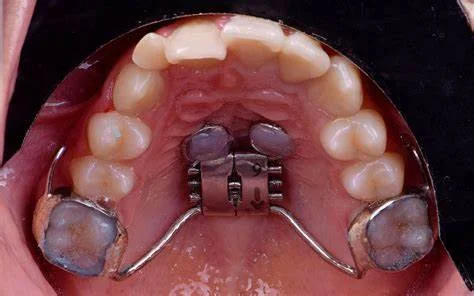

El sistema MARPE (Micro-Implant Assisted Rapid Palatal Expansion) es una técnica avanzada en ortodoncia que se utiliza para expandir el paladar de manera rápida y efectiva, principalmente en adolescentes y adultos jóvenes, donde los métodos tradicionales pueden ser menos efectivos debido a la madurez del hueso palatino. También es una alternativa efectiva y menos invasiva para corregir problemas de mordida. Conocida como expansión palatina asistida por microimplantes, esta técnica utiliza pequeños dispositivos anclados en el paladar para expandir gradualmente el hueso y crear más espacio para los dientes.

Componentes del Sistema MARPE

- Disyuntor Palatino: Un aparato expansor que se coloca en el paladar.

- Micro-implantes: Pequeños tornillos (mini-implantes) que se insertan en el hueso palatino para proporcionar anclaje adicional.

- Colocación del Disyuntor y Micro-implantes:

- El disyuntor palatino se coloca en la parte superior del paladar. Este aparato está diseñado con orificios para permitir la inserción de los micro-implantes.

- Los micro-implantes se insertan en el hueso palatino a través de los orificios del disyuntor, asegurando un anclaje firme y estable. Esto generalmente se realiza bajo anestesia local.